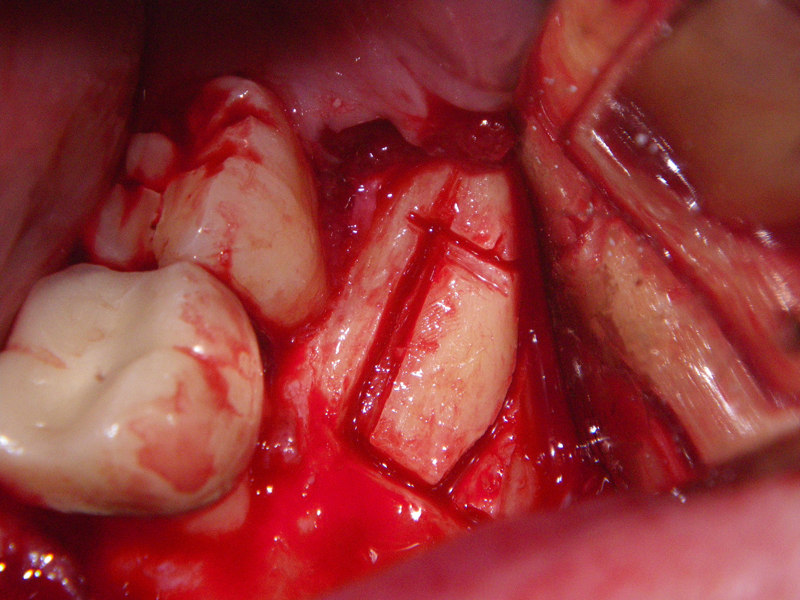

- Incision

- Identify, don’t ‘skeletonize,’ mental nerves

- Midline, lateral score marks

- Osteotomy 5 mm below tooth apices & mental nerve

- Angulation of cut (Depends on planned movement)

- Downfracture (release ‘wings’)

- Fixation (plate, screws, wire)

- Layered closure (mentalis)